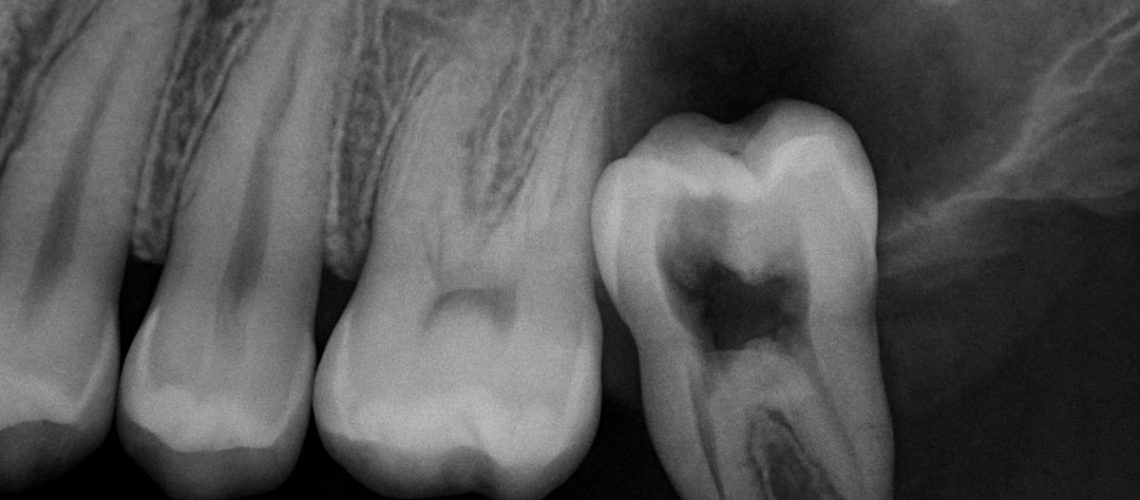

Tooth infection or abscess

Deep decay or a cracked molar lets bacteria reach the tooth’s nerve. The body responds with an abscess — a pus-filled pocket that pushes on nearby gum tissue and causes noticeable swelling and throbbing pain.